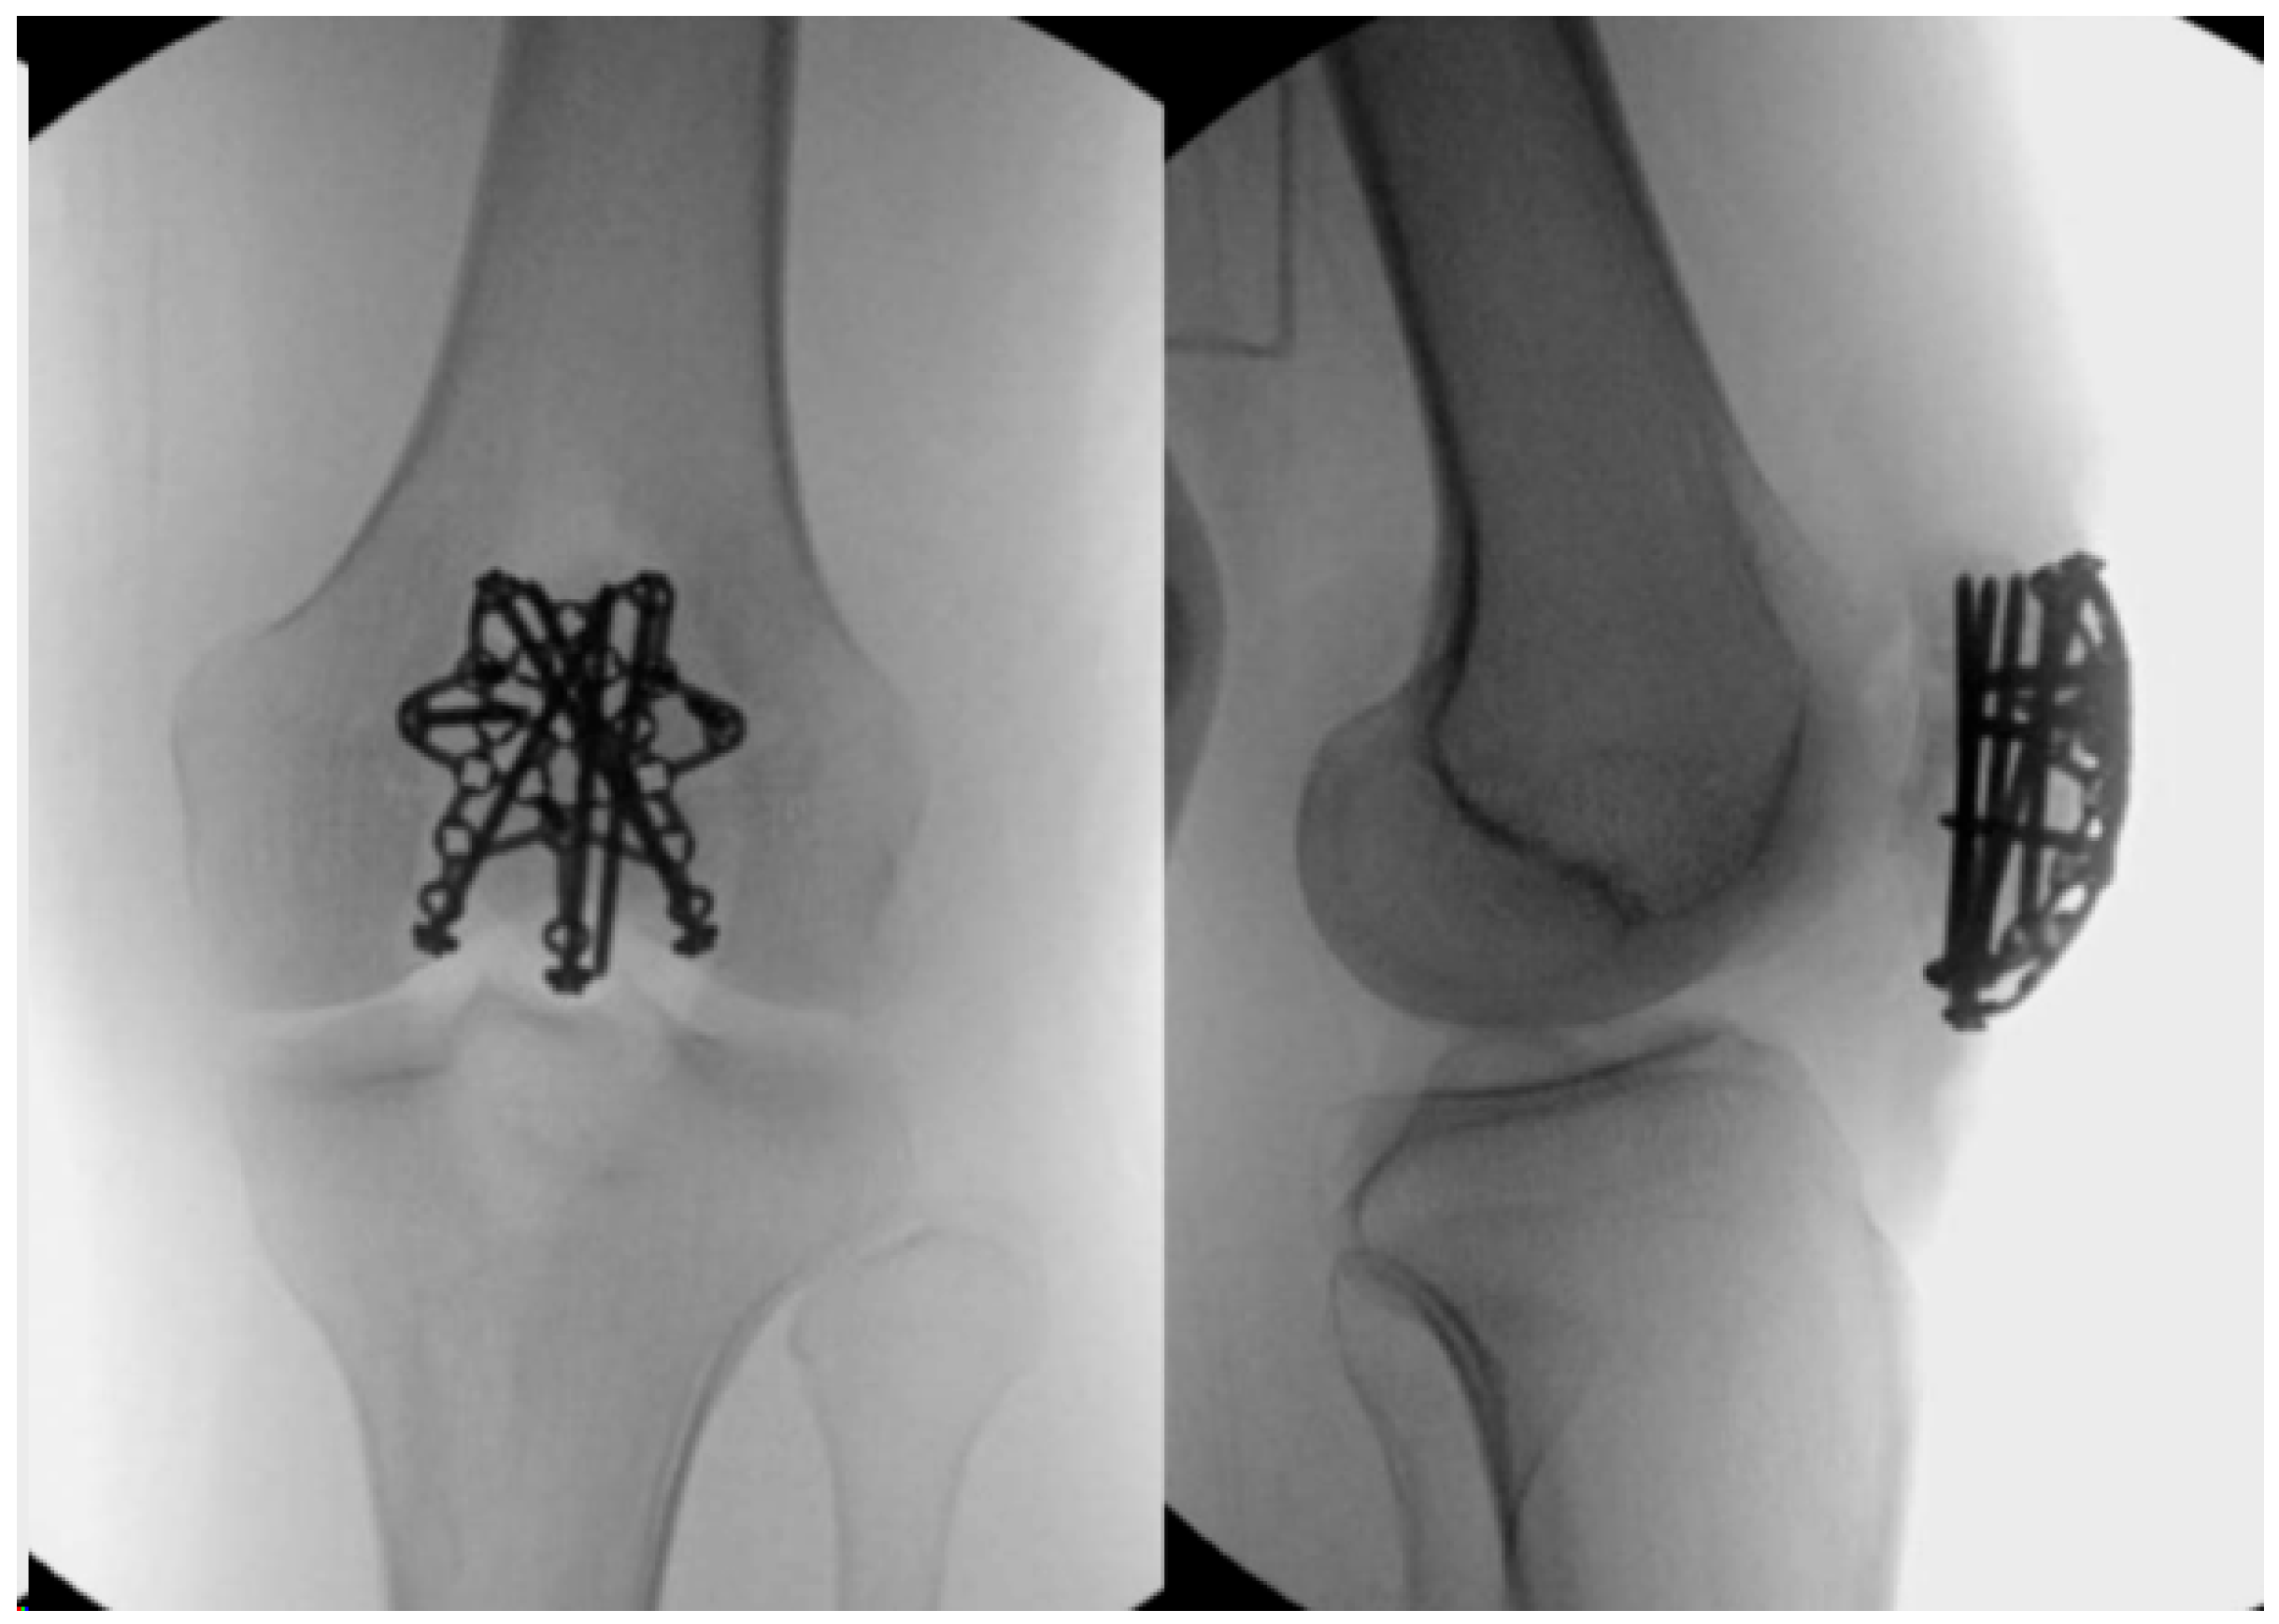

2.5. Locking Plates

- Wild, M.; Fischer, K.; Hilsenbeck, F.; Hakimi, M.; Betsch, M. Treating patella fractures with a fixed-angle patella plate-A prospective observational study. Injury 2016, 47, 1737–1743. [Google Scholar] [CrossRef] [PubMed]

- Buschbeck, S.; Götz, K.; Klug, A.; Barzen, S.; Gramlich, Y.; Hoffmann, R. Comminuted AO-C3 fractures of the patella: Good outcome using anatomically contoured locking plate fixation. Int. Orthop. 2022, 46, 1395–1403. [Google Scholar] [CrossRef]

- Yoo, S.J.; Ok, S.; Lee, J.; Choi, S. Can multiple miniplates improve the treatment of comminuted patellar fracture? BMC Musculoskelet. Disord. 2023, 24, 936. [Google Scholar] [CrossRef] [PubMed]

- Amin, A.; Kellam, P.J.; Warner, S.J. Treatment of a Multifragmentary Patella Fracture Using a Novel Anatomic Locking Plate. J. Orthop. Trauma 2022. [Google Scholar]

- Ellwein, A.; Lill, H.; DeyHazra, R.O.; Smith, T.; Katthagen, J.C. Outcomes after locked plating of displaced patella fractures: A prospective case series. Int. Orthop. 2019, 43, 2807–2815. [Google Scholar] [CrossRef] [PubMed]

- Wagner, F.C.; Neumann, M.V.; Wolf, S.; Jonaszik, A.; Izadpanah, K.; Piatek, S.; Südkamp, N.P. Biomechanical comparison of a 3.5 mm anterior locking plate to cannulated screws with anterior tension band wiring in comminuted patellar fractures. Injury 2020, 51, 1281–1287. [Google Scholar] [CrossRef] [PubMed]

- Lorich, D.G.; Fabricant, P.D.; Sauro, G.; Lazaro, L.E.; Thacher, R.R.; Garner, M.R.; Warner, S.J. Superior outcomes after operative fixation of patella fractures using a novel plating technique: A prospective cohort study. J. Orthop. Trauma 2017, 31, 241–247. [Google Scholar] [CrossRef]